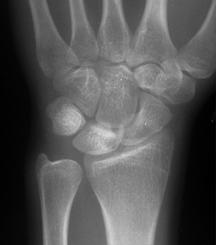

육체노동을 많이하는 남자에서 생기는 질환입니다. ulnar impaction syndrome 과는 반대로 ulna variance가 음성인 경우가 많으며

정맥 관류 차단에 의한 골내압력증가로 인하여 괴사가 진행된다고 추측하고 있는 질병입니다.

증상으로는 파악력이 감소되며 수근 관절 굴곡 제한이 많이 있습니다.

치료가 단계마다 다르기 때문에 분류가 중요합니다.